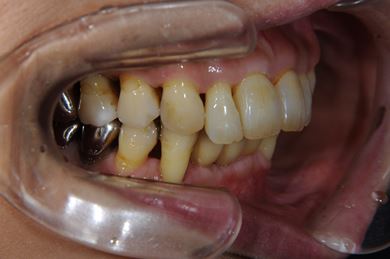

部分矯正治療+骨再生インプラント治療

| 主訴 | 上前歯の歯並びが気になる | ||||||||||||||||||||||||||||||||

| 治療方針 | 全体的に骨が薄く、なるべく歯に負担を立てない治療計画にしました。口元も下げたいため、歯を少し細く削り後ろにさげました。部分矯正後、下顎のインプラントも併用しています。 | ||||||||||||||||||||||||||||||||

| 治療内容 | 部分矯正(唇側矯正ホワイト)、インプラント2本(GBR)、メタルボンドセラミッククラウン3本 | ||||||||||||||||||||||||||||||||